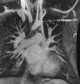

Pulmonary artery coarctation

Coarctation of the aorta (CoA or CoAo), also called aortic narrowing, is a congenital condition whereby the aorta is narrow, usually in the area where the ductus arteriosus (ligamentum arteriosum after regression) inserts. The word coarctation means "pressing or drawing together; narrowing". [Source: Wikipedia ]